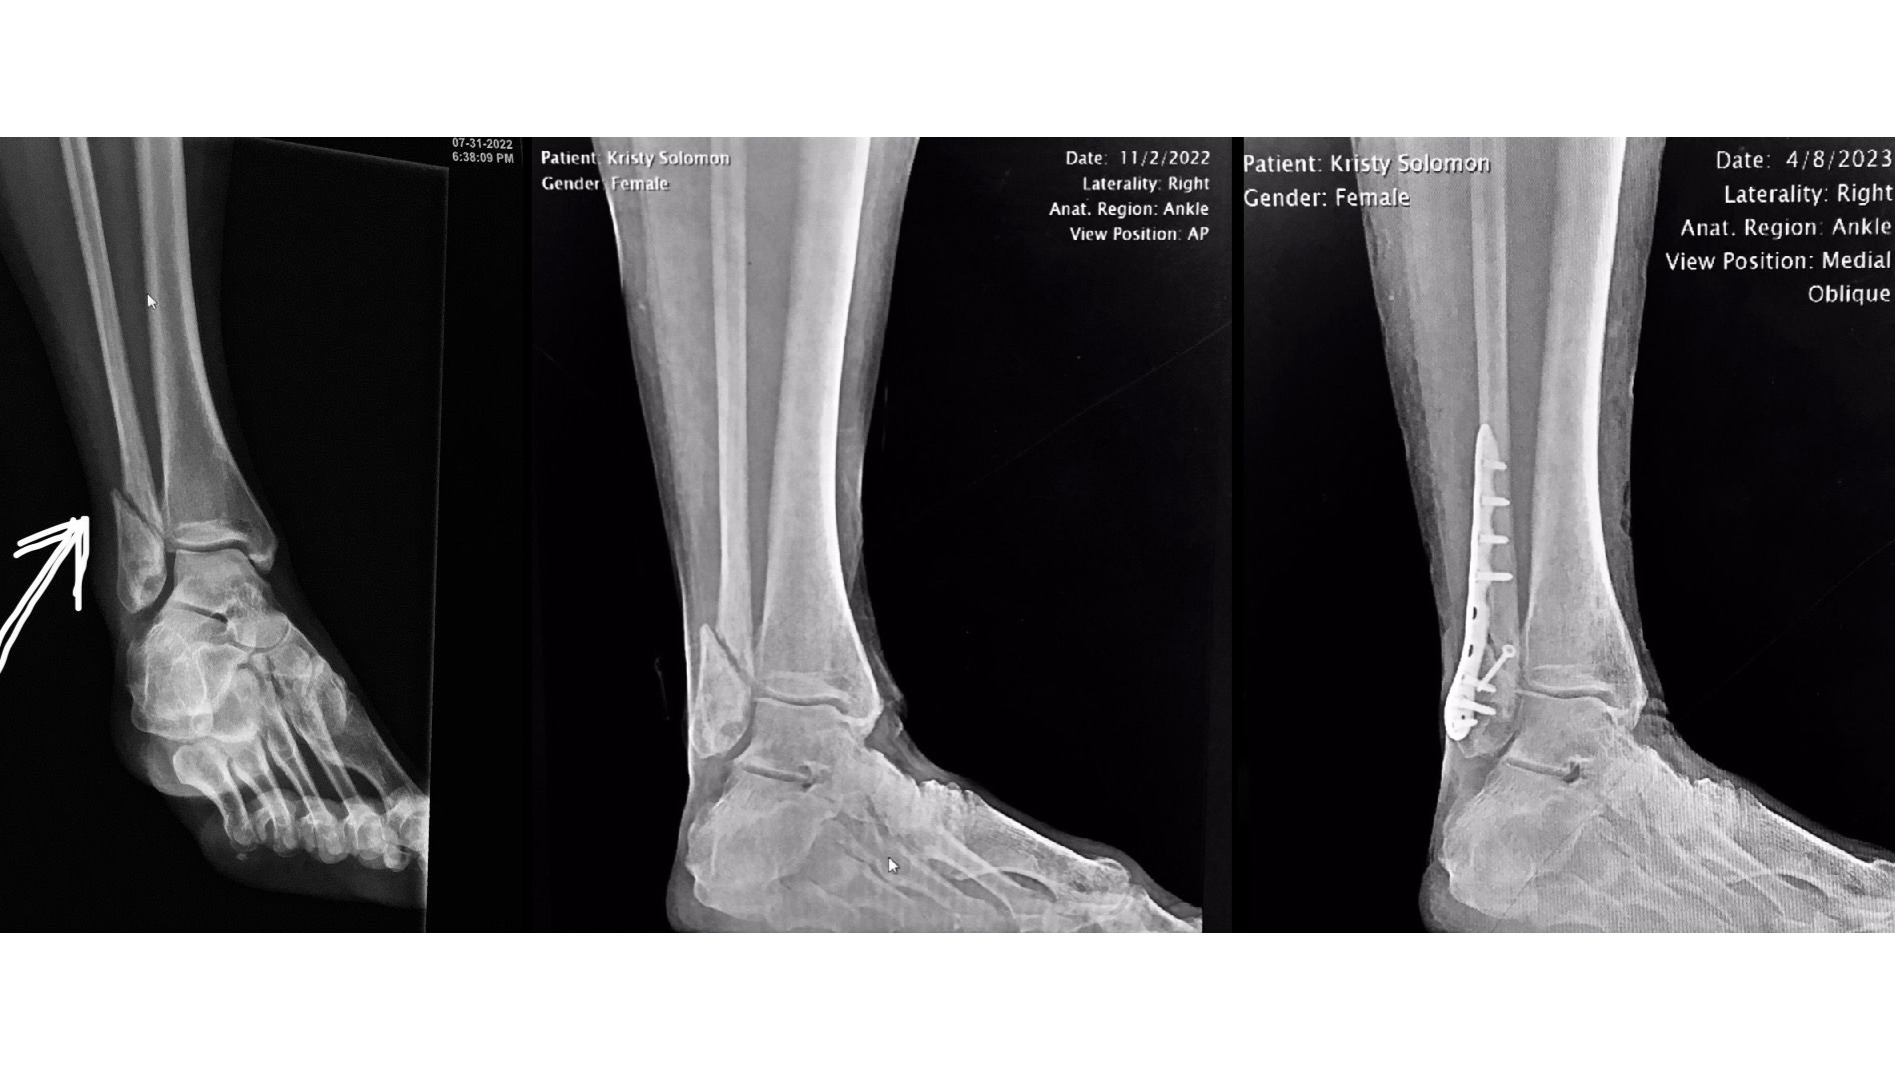

As some of you may know, my sister Kristy suffered a pretty bad ankle break last July, 7/31/2022. She was with a friend enjoying one of her favorite pastimes- a hike upstate on a rare weekend off from work when she slipped on her descent from Millbrook Mountain. The foot carrying her weight slid in front of her causing her ankle to audibly snap as it formed a 90-degree angle (later to find out that the fibula was broken into two pieces). Adrenaline carried her through the duration of the hike out after which she went straight to the ER, but little has supported her up until now. In fact, it has been an arduous uphill battle my sister has endured these past 10 months.

Kristy initially saw an orthopedic surgeon who put her in a walking boot and expected her to heal. Four months later, the X-rays showed zero bone growth and provided proof of the extremely poor care she, unfortunately, received from that provider. Resulting second and third opinions both stated that the bone would never heal this way and that surgery was needed from the beginning. Five months, one titanium plate, 10 screws and a whole lot of frustration and discomfort after the slip on the mountain, Kristy began her healing journey- again.